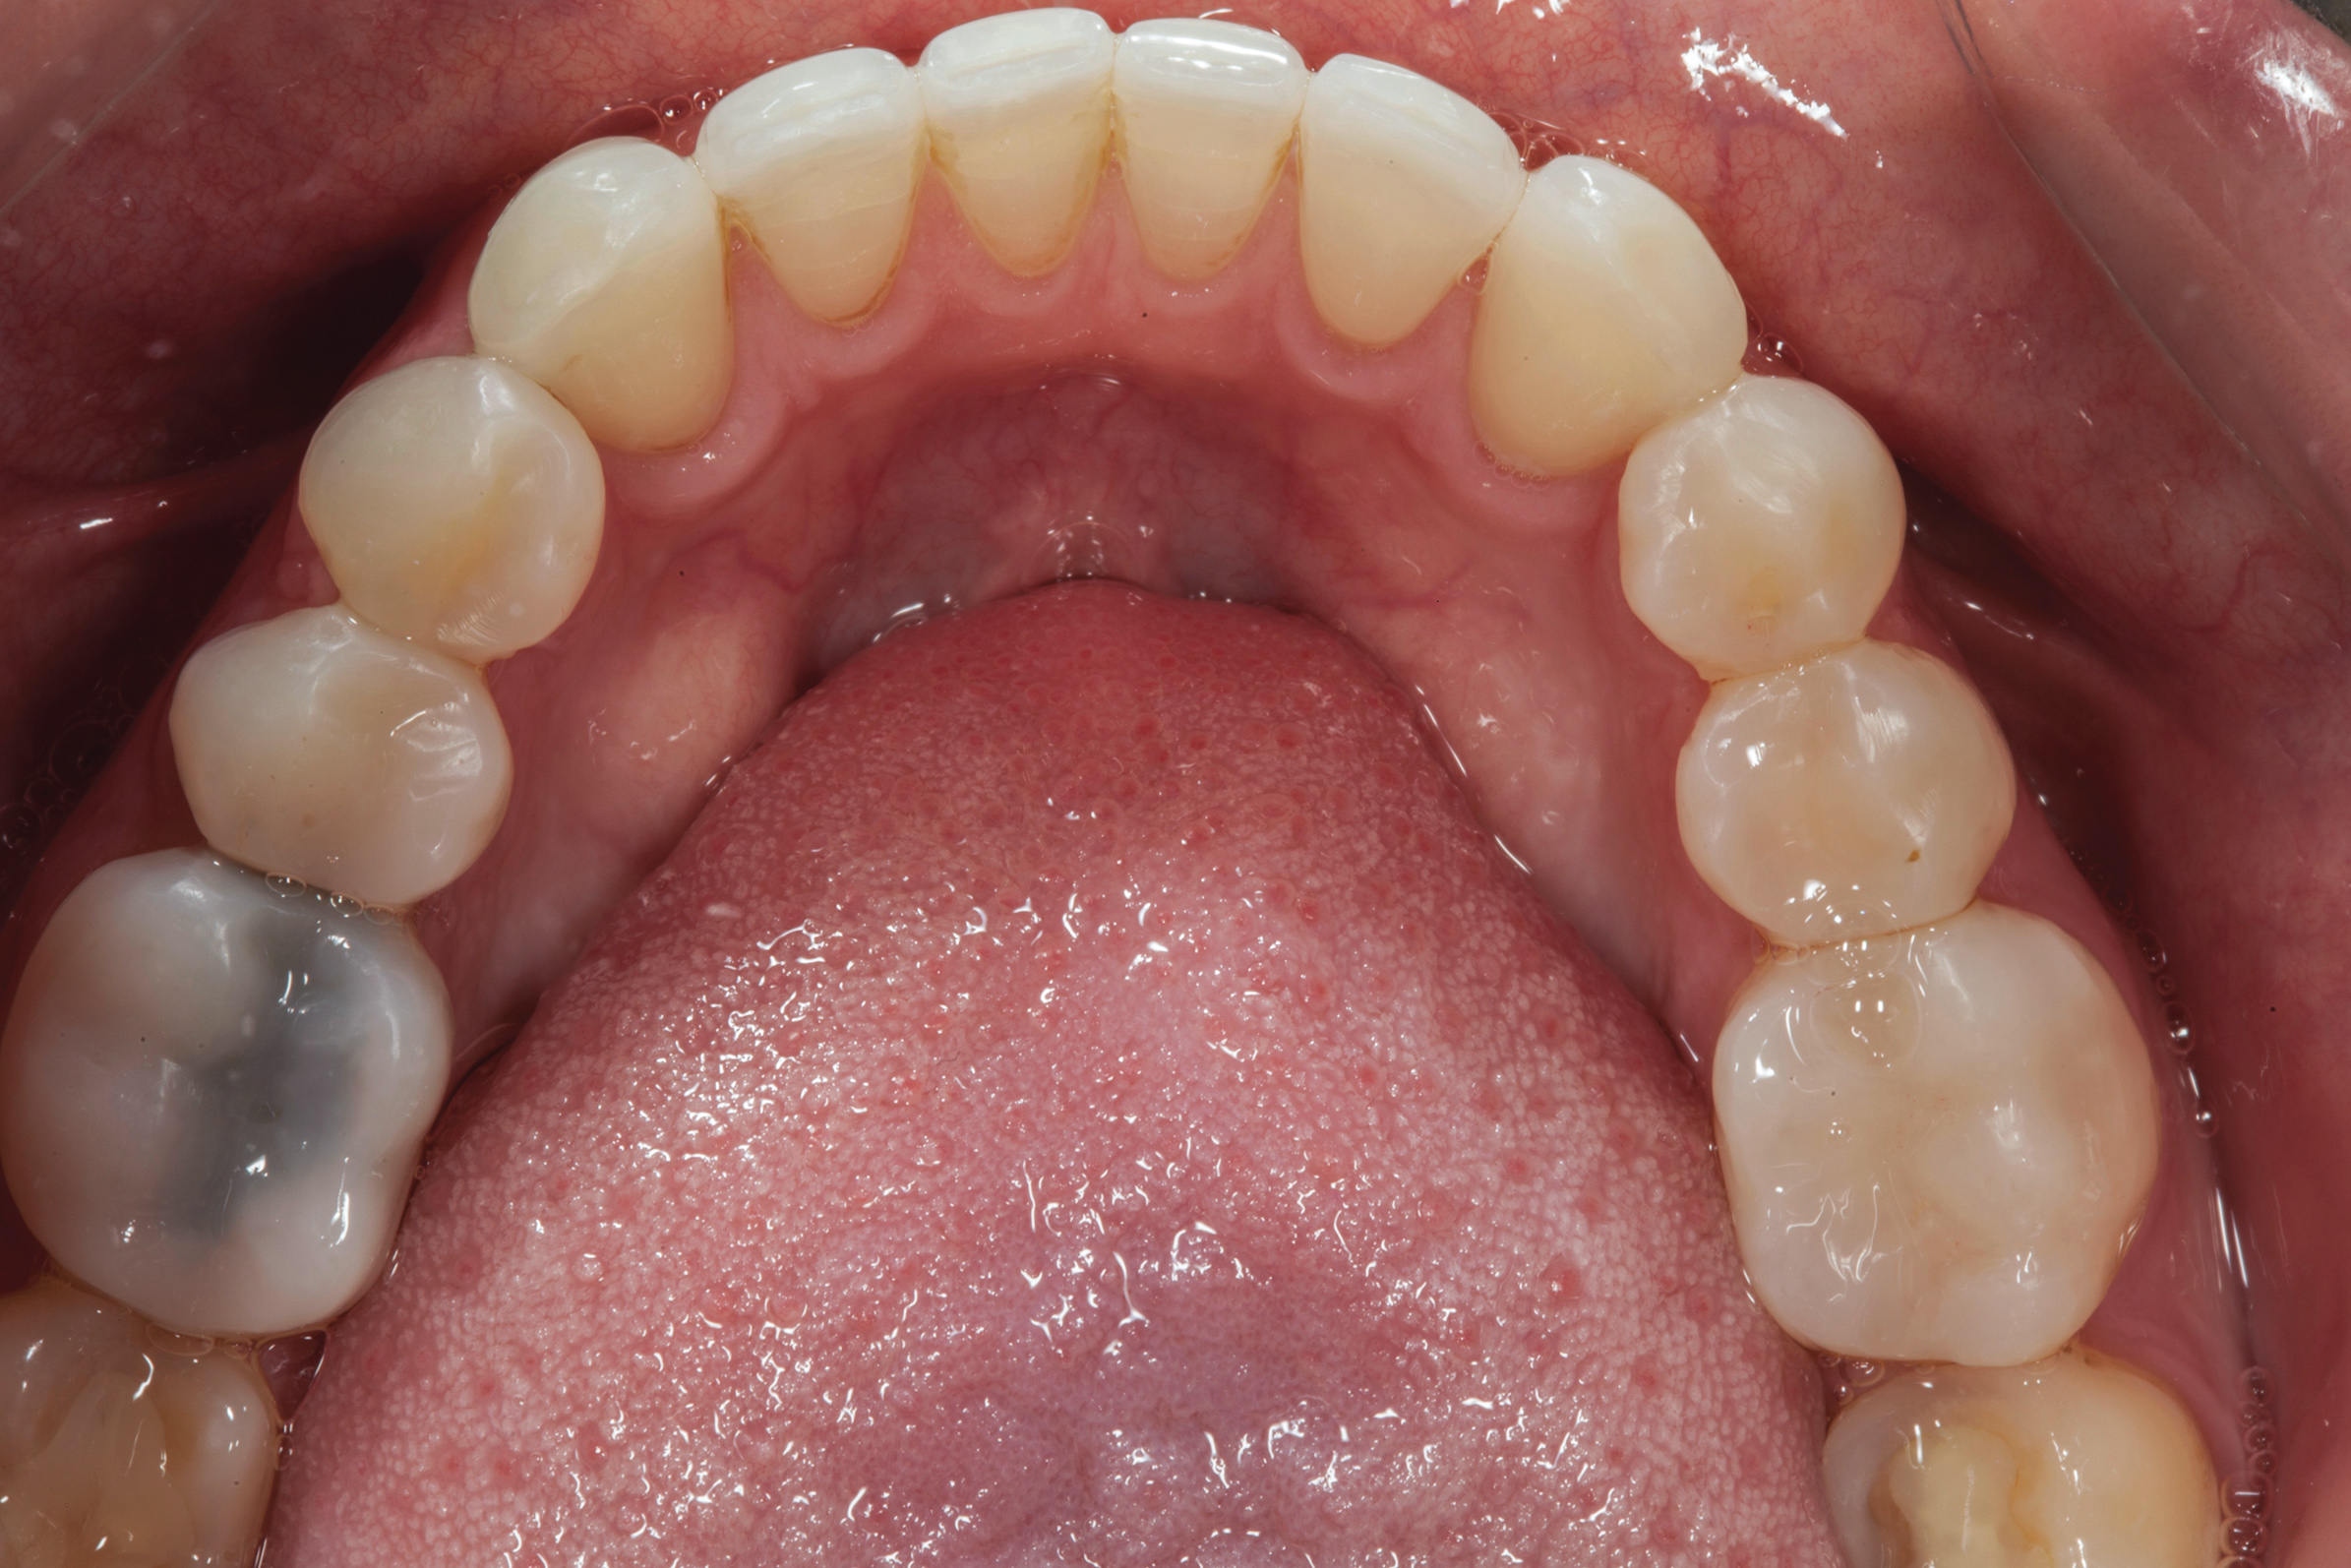

After the composite veneers were finalized, impressions were taken for a monolithic lithium disilicate crown on tooth No. 12. This was placed during a subsequent appointment, and occlusal equilibration was carried out. The patient returned for final photographs a couple of weeks later (Figure 10 through Figure 14).

(13.) Postoperative occlusal view of upper arch.

Figure 13